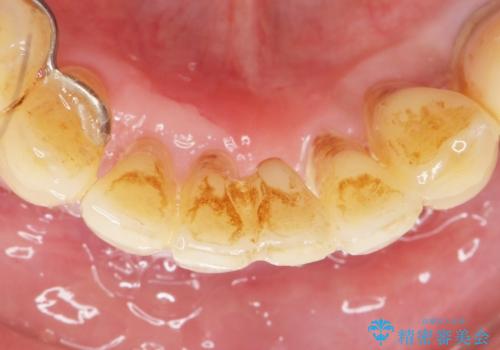

- 歯がぐらぐらで咬めないことを主訴に来院された患者様です。

仕事が忙しくなかなか自分のことに気が回らなかったそうですが、どんどん歯の動揺が増し「もう限界だ!」と思い受診を決断したとのことでした。

精査したところ、全顎的な重度の歯周病により下顎前歯に激しい動揺を認めました。